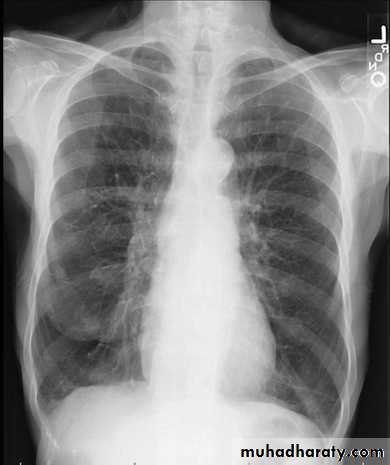

Except in the case of very advanced disease with bulla formation, chest radiography does not image emphysema directly, but rather infers the diagnosis due to associated features :

hyperinflation:

1.flattened hemidiaphragm(s): most reliable sign

2.ncreased and usually irregular radiolucency of the lungs

3.increased retrosternal airspace

4.increased antero-posterior diameter of chest

5.widely spaced ribs

6.sternal bowing

7.tenting of the diaphragm

8.saber-sheath trachea

9.vascular changes paucity of blood vessels ( absent pulmonary markings in outer 1/3 of the lung fields )

10 .pulmonary arterial hypertension

pruning of peripheral vessels

increased calibre of central arteries

right ventricular enlargement